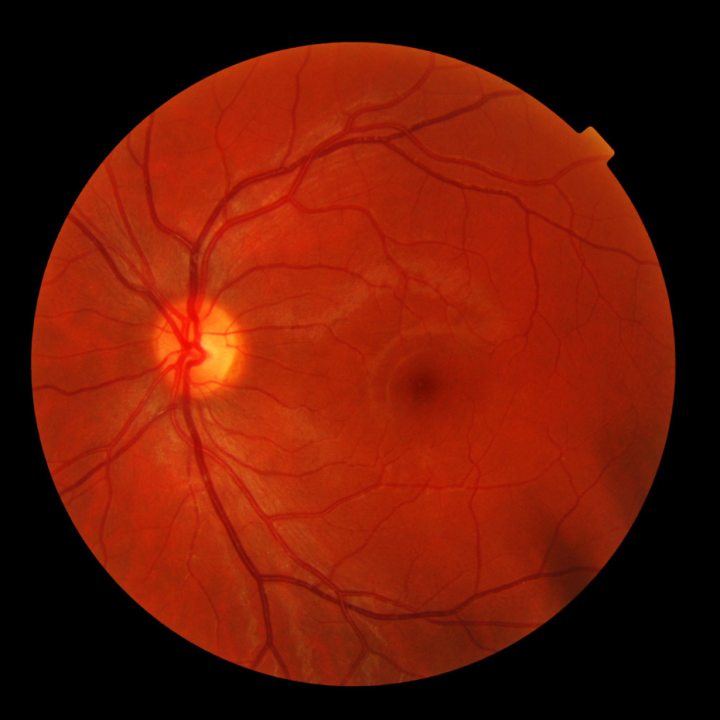

Un examen de la vista le permite a su oftalmólogo (optometrista u oftalmólogo) ver toda su retina. La detección temprana, el tratamiento oportuno y el seguimiento adecuado con su oftalmólogo pueden reducir el riesgo de pérdida grave de la visión debido a enfermedades oculares relacionadas con la diabetes.